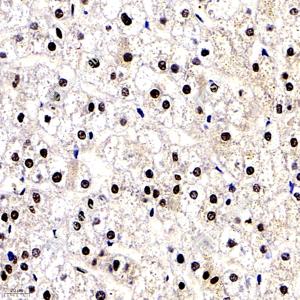

IHC检测MEK1蛋白(货号 GB11304). 样品: 人肝, 4%多聚甲醛 (货号G1101) 固定12-24小时. 抗原修复: 柠檬酸抗原修复液(干粉, pH 6.0) (G1201), 98℃, 20分钟. —抗: 1: 300稀释, 4℃ 孵育过夜. 二抗: HRP标记山羊抗兔IgG (H+L) (货号GB23303), 1: 200稀释, 室温孵育1小时. |